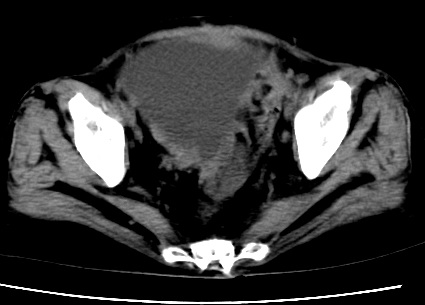

标题: CT23975:女61岁,腹部不适,明显消瘦

既往5年前卵巢癌行子宫及附件切除,右乳癌术后一年,考虑腹膜转移?

大量腹水,考虑腹膜转移。肝脏低密度灶。1囊肿,2转移。

1)结合病史,考虑腹膜及网膜转移瘤。2)肝脏多发性低密度灶,不排除转移瘤。3)大量腹水。

考虑卵巢癌行子宫术后复发,并肝、腹腔 、大网膜转移可能性大。

大量腹水。